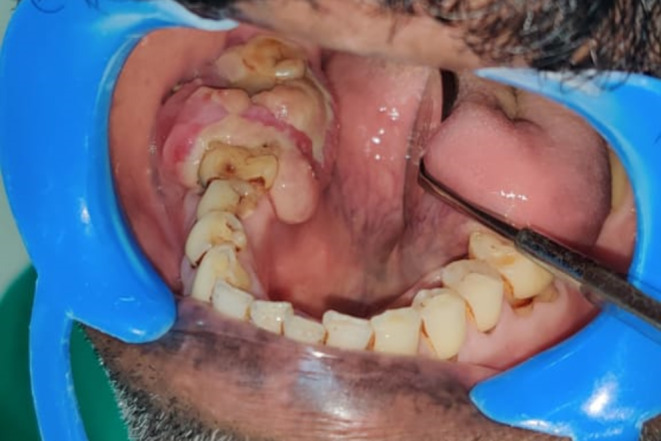

A 55-year-old male was referred with a 20-day history of growth in the right lower jaw following the extraction of right mandibular second molar. On intraoral examination, a proliferative mass was observed on the residual alveoli, accompanied by vestibular obliteration (Fig. 1). An orthopantomogram (OPG) revealed diffuse radiolucency adjacent to tooth 47 (equivalent to tooth 31 by ADA numbering) and an altered bony pattern (Fig. 2). Given the rapidly expanding mass, the clinical diagnosis was a minor salivary gland malignancy, likely primary adenocarcinoma.

Fig. 1.

A proliferative mass on the residual alveolar ridge of the right mandibular arch, with vestibular obliteration